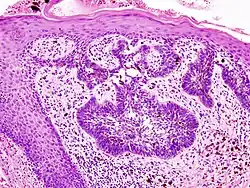

Basal cell carcinoma of the skin, cell nuclei (blue-purple), extracellular material (pink)